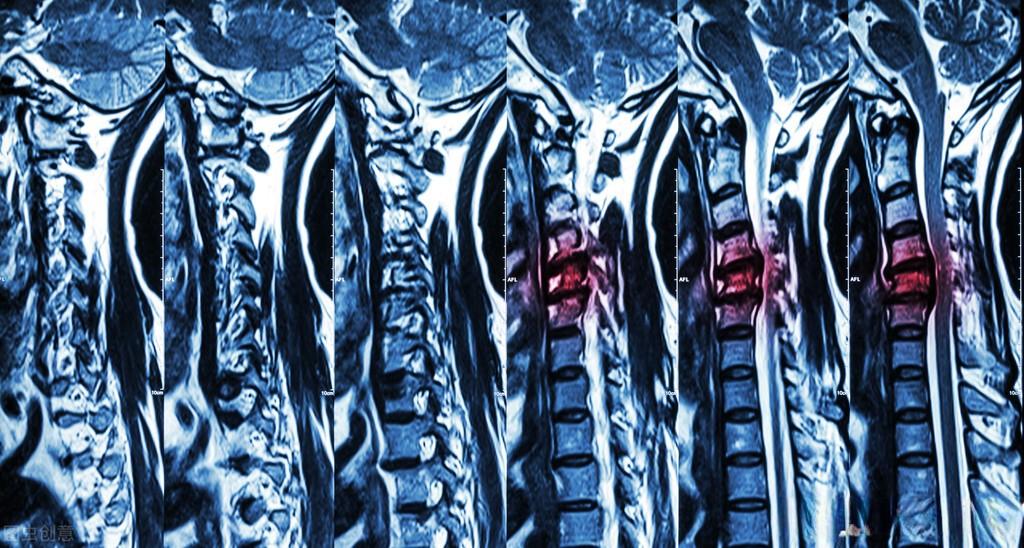

脊髓亚急性联合变性是一种由维生素B12缺乏引起的进展性脊髓病,患者可能面临瘫痪的危险。然而,这种疾病如果得到及时诊断和治疗,患者完全有可能重新站起来。让我们通过一个真实的康复案例,来了解这种疾病的治疗过程。

脊髓亚急性联合变性的原因主要是维生素B12缺乏。这种维生素对神经髓鞘的形成至关重要,缺乏会导致神经病变。常见的原因包括摄入不足(如长期素食)、吸收障碍(如胃大部切除术后)、结合障碍等。治疗的关键是早期诊断和及时补充维生素B12。如果在发病3个月内得到积极治疗,大多数患者可以完全恢复。然而,如果延误治疗,可能会留下不可逆的神经功能缺损。